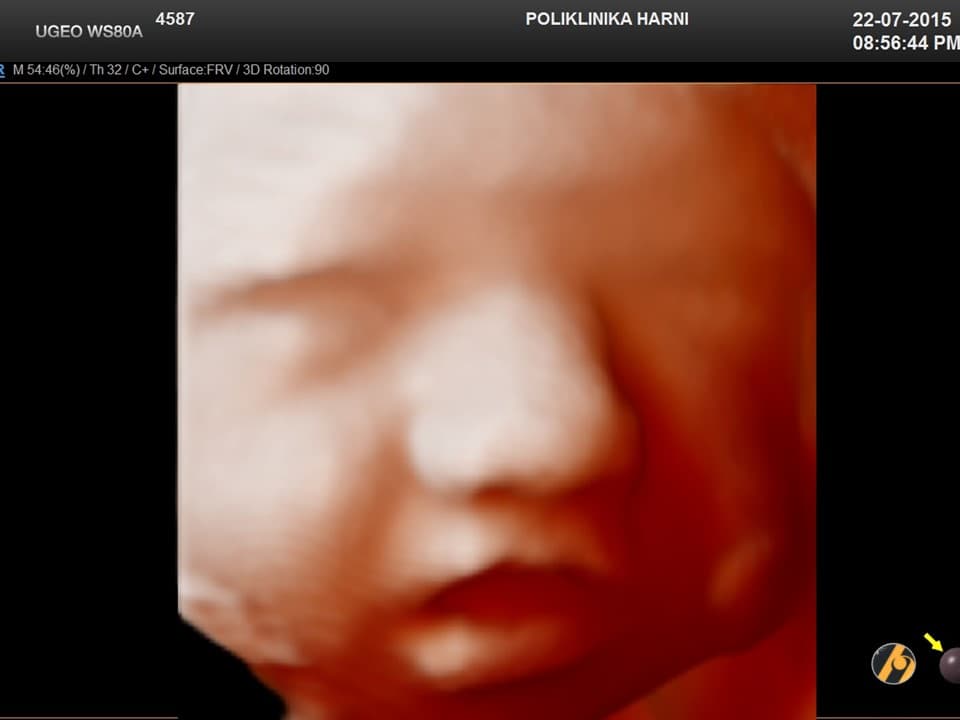

U ovom tjednu vaša beba gleda vodeni svijet koji je okružuje, čuje kruljenje iz vašeg trbuha, otkucaje vašeg srca i vaš glas, i osjeti dodir kada uhvati prst i sisa palac.

Vaša beba dugačka je oko 42 cm, i teška 1,800 – 2,000 g.